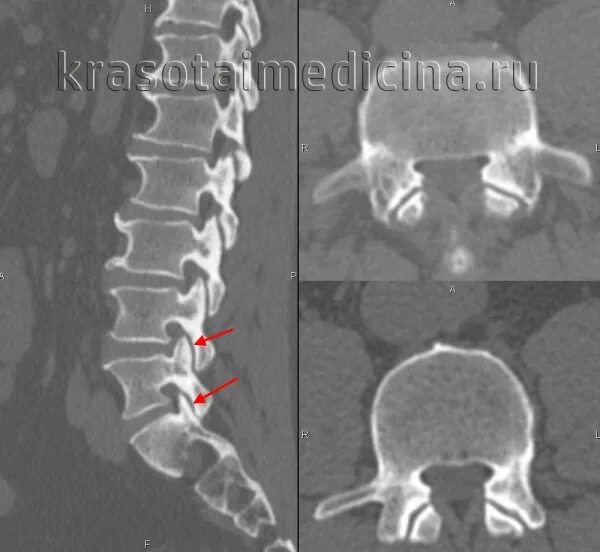

Спондилоартроз шейного позвоночника